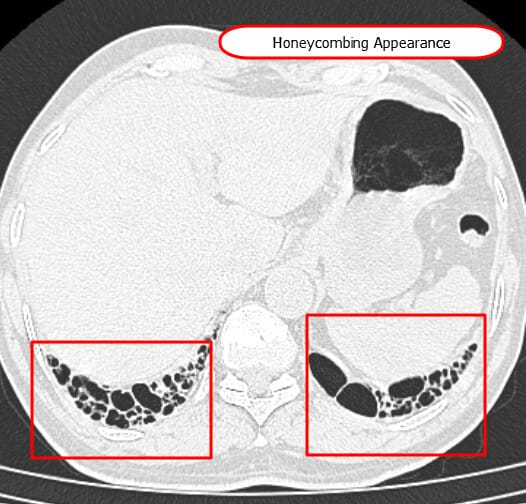

간질성 폐질환 (ILD)의 HRCT 영상 소견

고해상도 흉부 CT(High Resolution CT, HRCT)을 시행하여 IPF 여부를 확인합니다. (IPF에서는 Honeycombing appearance가 특징적으로 관찰됩니다)

- 벌집양(honeycombing): IPF (UIP)의 핵심 소견

| 벌집양 소견 (Honeycombing) – IPF , UIP의 소견 |

| 🔵 말기 폐섬유화의 특징으로, 기저부 주변에 다수의 작은 낭포성 공간들이 겹겹이 배열된 모습을 보입니다. |

| 기저부와 주변부를 따라 규칙적으로 배치된 다수의 원형 또는 불규칙한 낭포들이 관찰됩니다. |